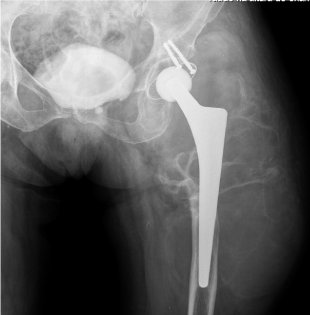

We present an 82-year-old woman with a history of hip arthroplasty due to femur fracture during a road accident 30 years ago. She was admitted to a hospital for fever, asthenia and a large swelling in the hip. Analytic study revealed microcytic anemia and the Computed tomography showed a 7.9 inches mass surrounding the arthroplasty. It was diagnosed a Pseudotumor associated with the hip arthroplasty. After the surgical resection of the lesion and revision of the arthroplasty, the patient underwent a rehabilitation program, with good clinical results. Nowadays, she is asymptomatic and recovered its functionality and quality of life (Figure 1).

Figure 1: Pseudotumor of the hip after arthroplasty.